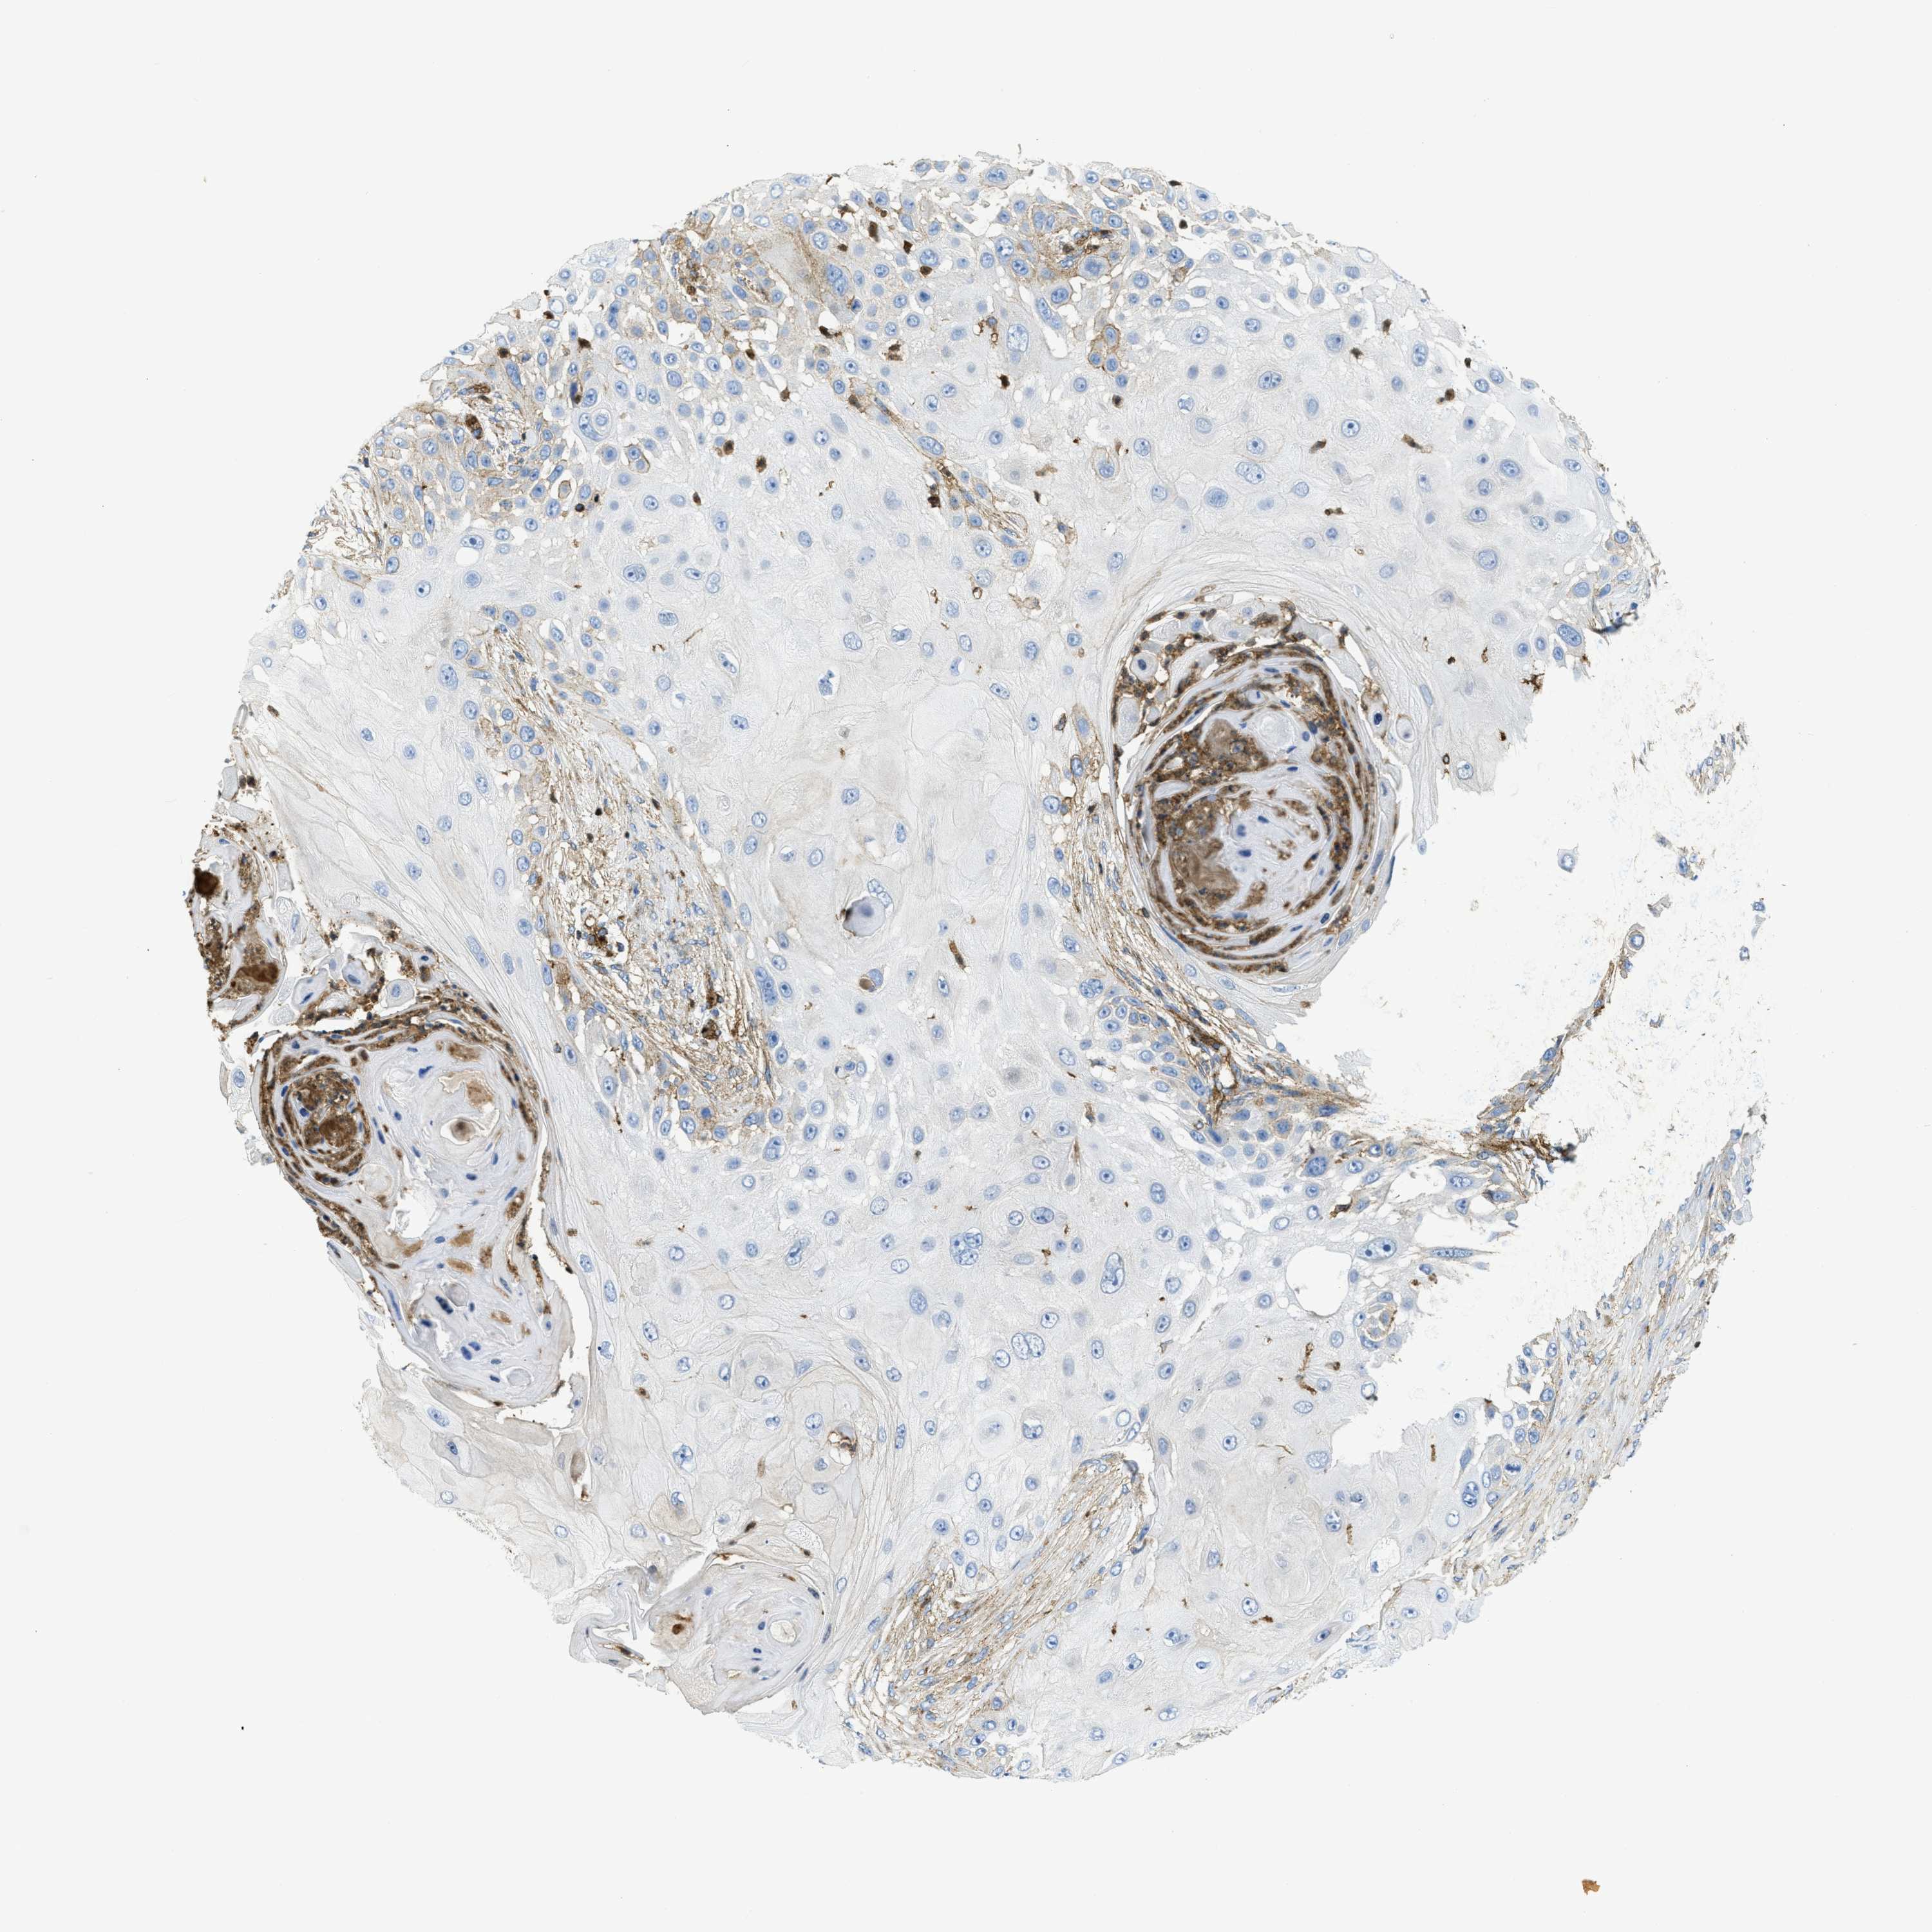

SKIN CANCER - Protein expressioni

A mouse-over function shows sample information and annotation data. Click on an image to view it in a full screen mode. Samples can be filtered based on level of antibody staining by selecting one or several of the following categories: high, medium, low and not detected. The assay and annotation is described here.

Each image is clickable and will lead to virtual microscopy that enables deeper exploration of all samples and also displays staining intensity scores, fraction scores and subcellular localization as well as patient and tissue information for each sample.

Antibody HPA017964

Staining

High

Medium

Low

Not detected

Intensity

Strong

Moderate

Weak

Negative

Quantity

>75%

75%-25%

<25%

None

Location

Nuclear

Cytoplasmic/membranous

Cytoplasmic/membranous,nuclear

Squamous cell carcinoma in situ, NOS

Squamous cell carcinoma, NOS

Squamous cell carcinoma, metastatic, NOS

Basal cell carcinoma

Adnexal tumor, benign